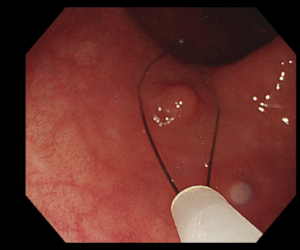

*Coldポリペクトミー

小さなポリープはスネアと呼ばれる細いワイヤーで絞扼し切り取ります